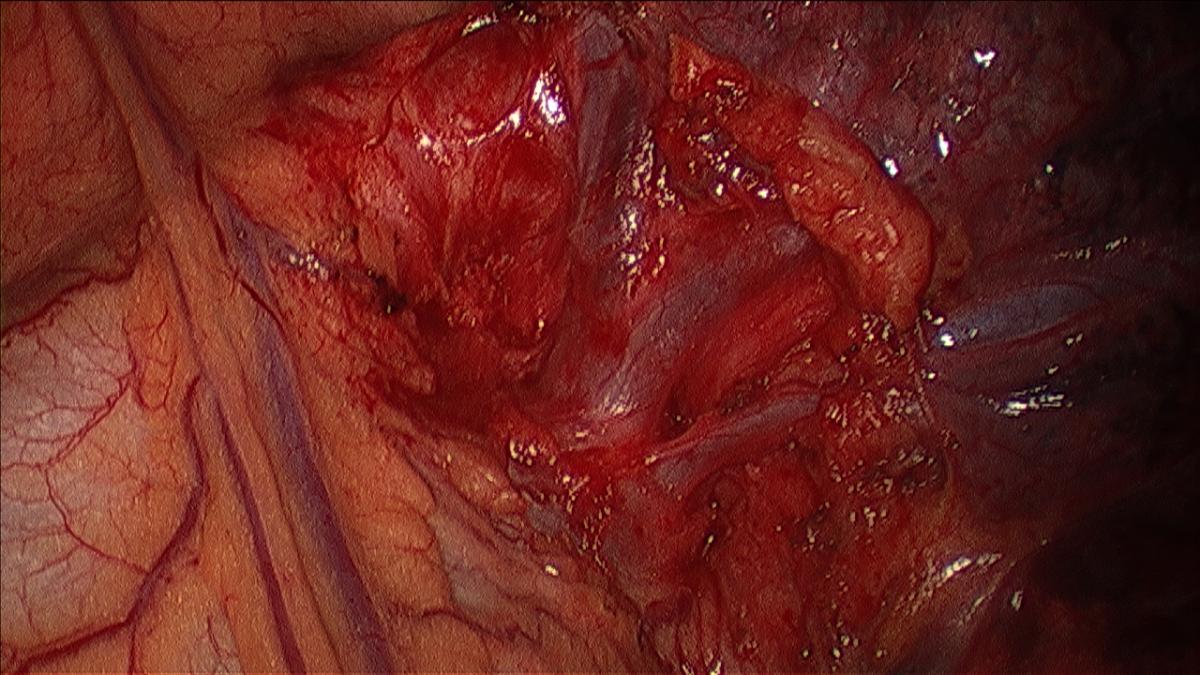

The left upper lobe has anatomically well-defined segments with a clear division of the hilar structures from the apical and lingular segments, allowing for an anatomical resection. The left apical tri-segments are the apico-posterior and the anterior segments of the upper lobe. These can be clearly isolated from the superior and inferior lingular segments, as the vasculature and airways are anatomically distinct from each other and can be clearly identified with surgical dissection. An alternate name for the operation is, therefore, lingular sparing left upper lobectomy (7). The lesion should be located well within the apical segments of the left upper lobe and be 1.5 cm or less in diameter. A CT scan is vital to aid in preoperative localization of the lesion and assessment of size and position within the lobe (Figure 1). Cross-sectional images, as well as coronal and sagittal imaging, should be used to confirm the position of the lesion, in addition to the vasculature and airway to the segments (6).

Figure 1: Anterior view of left hilum with phrenic nerve and pulmonary vein.